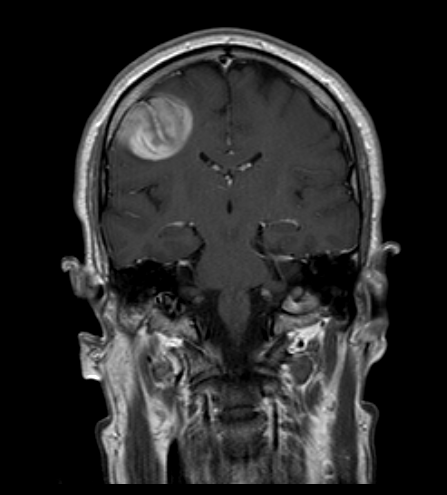

Resezione microchirurgica di tumore cerebrale (glioma alto grado cortico-sottocorticale) frontale dx